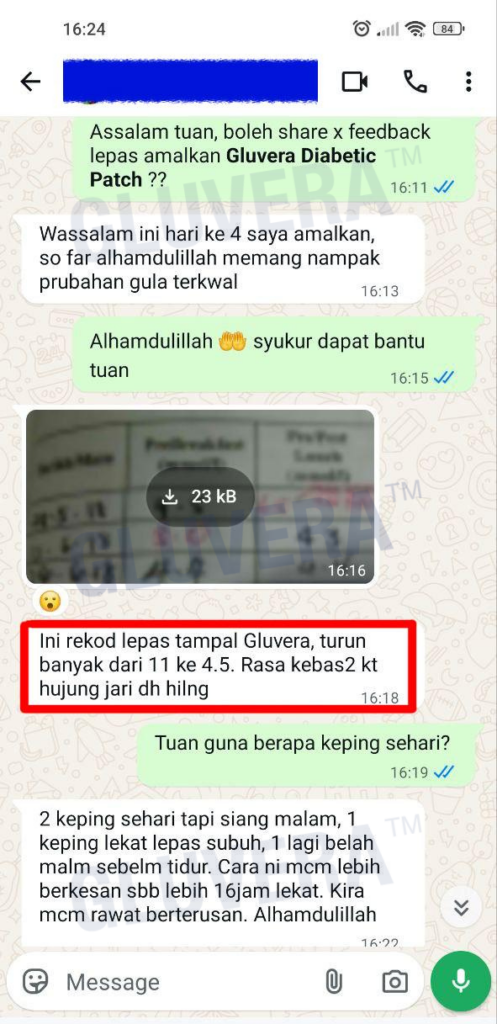

Individual results may vary, and testimonials are not claimed to represent typical results.

All testimonials are by real people, and may not reflect the typical purchaser’s experience, and are not intended to represent or guarantee that anyone will achieve the same or similar results.